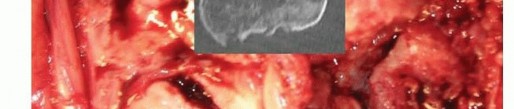

TECH FIG 3 •(continued)D. Comminuted distal humeral fracture in an osteoporotic elderly woman, with CT imaging confirming significant articular comminution. This is the view through the triceps split.

TECH FIG 4 • A. The humeral component entry point, the apex of the olecranon fossa, is identified, and humeral canal preparation is commenced by opening the canal with a bone nibbler or burr.(continued)